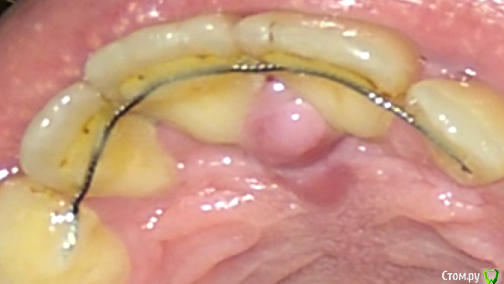

Anthonyc Опубликовано 10 марта, 2018 Поделиться Опубликовано 10 марта, 2018 (изменено) Здравствуйте! Меньше недели назад болел гриппом, пил лекарства...и заметил воспаление на верхнем небе по середине между двумя передними зубами. У меня раньше такое было, потом само проходило.Воспаление не проходит уже четвертый день, в самом начале даже жевать мешало, сейчас шишка стала меньше, утром , как только проснусь этот "шарик" увеличен в размерах, а днем становится меньше, вчера даже кровь вышла с десен в том месте. Не болит, но дискомфорт на психологическом уровне дает.Что это может быть? После гриппа я до конца еще не восстановился, может ли это быть как-то связано? P.S. Около 10 лет назад мне ставили брэкеты (передние зубы были деформированы вперед , т.к в детстве сосал палец), и в этом самом месте хирург что-то вырезал, что именно я не помню и для чего. Изменено 10 марта, 2018 пользователем Anthonyc Ссылка на комментарий

Anthonyc Опубликовано 14 марта, 2018 Автор Поделиться Опубликовано 14 марта, 2018 (изменено) А что собираются удалять?Еще у хирурга не был, но стоматолог сказала что вот это. Не знаю права ли она. Изменено 14 марта, 2018 пользователем Anthonyc Ссылка на комментарий

red_butler Опубликовано 15 марта, 2018 Поделиться Опубликовано 15 марта, 2018 это анатомическое образование, удалять не надо. Сделайте Rg. Вы со своим ортодонтом обсуждали срок ношения ретейнера, не пора снимать? Ссылка на комментарий

Anthonyc Опубликовано 15 марта, 2018 Автор Поделиться Опубликовано 15 марта, 2018 (изменено) это анатомическое образование, удалять не надо. Сделайте Rg. Вы со своим ортодонтом обсуждали срок ношения ретейнера, не пора снимать?Я так понял он на всю жизнь О_0, я его ношу уже 8-ой год, может он и не нужен уже.Это анатомическое образование уже вторую неделю не проходит, а после сна увеличено в размерах и как шарик. Днем становится мягче и шарик проходит. Изменено 15 марта, 2018 пользователем Anthonyc Ссылка на комментарий

shishok Опубликовано 20 марта, 2018 Поделиться Опубликовано 20 марта, 2018 Ретейнер мешает нормальной гигиене.Как следствие-воспаление слизистой(в данном случае-воспаление резцового сосочка). Ссылка на комментарий